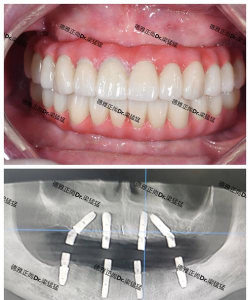

口碑与案例

天津美莱在天津地区口碑良好,成功案例丰富,患者满意度较高。